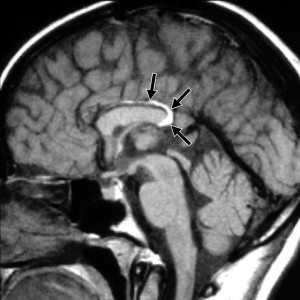

МРТ головного мозга. Т1-взвешенные корональная и сагиттальная МРТ. Эпидермоидная киста левой височной доли.